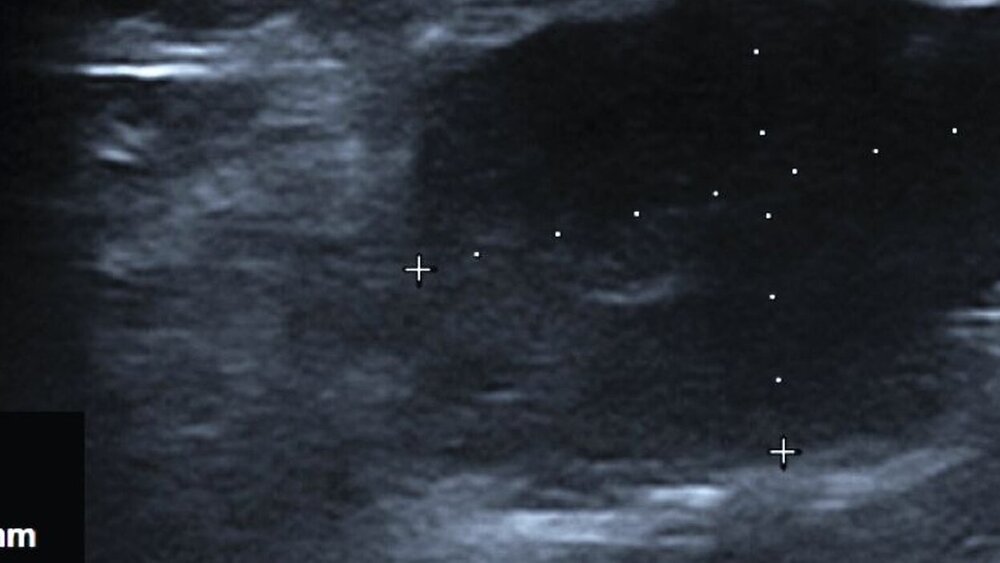

Sonografisch ließ sich eine 11,8 mm x 17,4 mm messende, scharf begrenzte, echoarme Raumforderung ohne nachweisliche Vaskularisierung mit dezenter dorsaler Schallverstärkung darstellen (Abbildung 1). Aufgrund des ungewöhnlich schnellen Wachstums erfolgte zum Ausschluss einer malignen Ursache sowie einer differenzialdiagnostisch in Betracht gezogenen Speichelretentionszyste die radiologische Bildgebung in Form eines Kontrastmittel-verstärkten MRTs. Dabei zeigte sich eine multilobulierte Läsion ventral am Musculus masseter ohne pathognomonische Morphologie, die in nativer T1-Wichtung isointens zum subkutanen Fettgewebe imponierte, mit flächiger Signalsteigerung nach Kontrastmittelgabe (Abbildung 2). Korrelierend dazu wurde eine deutliche restriktive Diffusionsstörung nachgewiesen, weshalb differenzialdiagnostisch nun vorrangig maligne Raumforderungen wie ein Liposarkom oder ein adenoidzystisches Karzinom diskutiert wurden. Eine (teil-)thrombosierte vaskuläre Malformation wurde allerdings ebenso in Betracht gezogen.